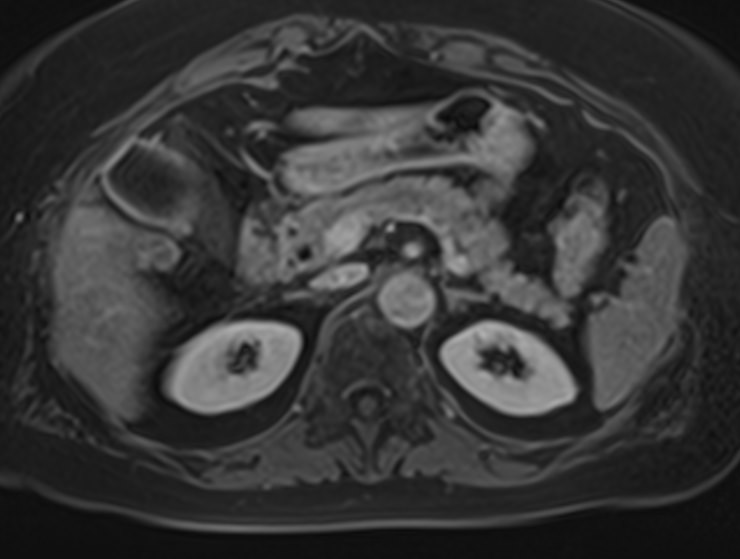

Для расширения возможностей диагностики, при необходимости уточнения характера патологических изменений, в случае подозрения на опухолевый процесс, дополнительно применяется внутривенное контрастное усиление.

Для этого в вену вводится контрастный препарат, содержащий соединения металла гадолиния (Магневист, Гадовист, Омнискан и др). Степень и характер накопления контрастного препарата в органах и тканях позволяет различать патологические процессы и дает возможность, в частности, диагностировать патологические очаги минимальных размеров, что бывает особенно важно в ранней диагностике опухолей.